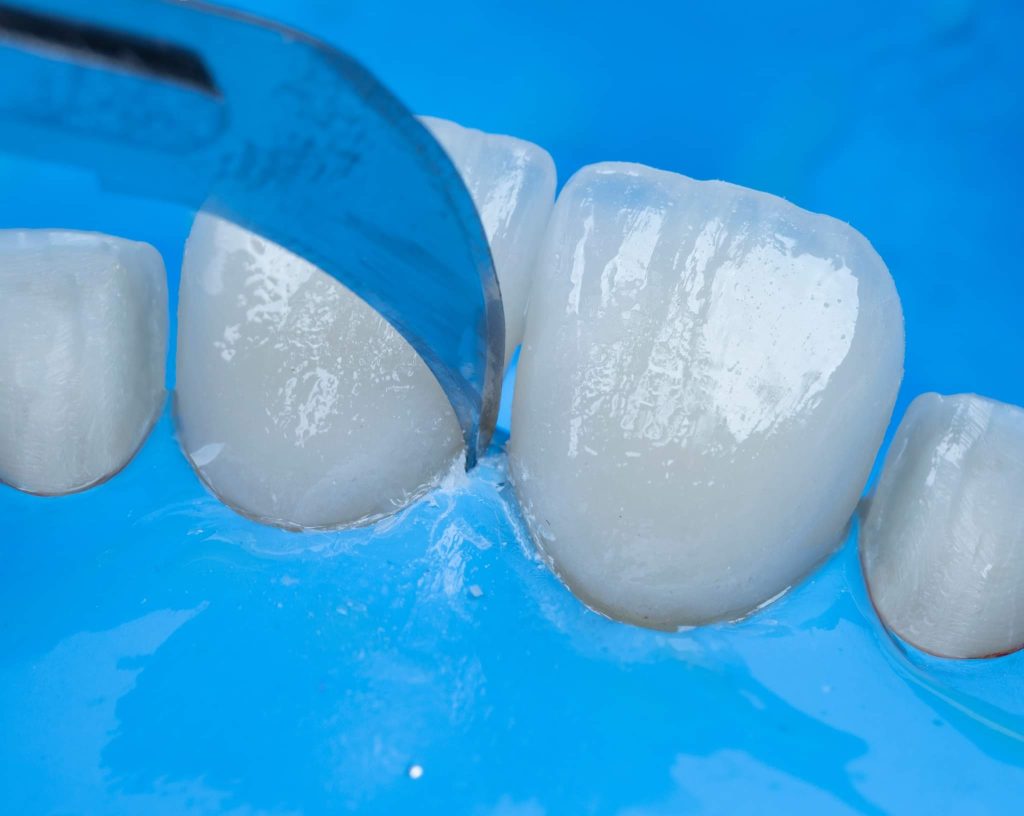

A veneer may be defined as anything that is covering something to improve its appearance. Within dentistry, a veneer is a thin layer of ceramic or composite resin placed on the facial surface of one or more teeth. The thickness can be ranged from 0.3-0.7mm.

The case presented in this case report is for a 27-years-old female patient with a chief complaint of aesthetic correction for her smile. The patient was unhappy with her smile. After clinical examination, there were previous old composite veneering done poorly and incorrectly to close the multiple interdental spacing. After discussing the various treatment options (i.e., orthodontic treatment, direct, or indirect veneers), indirect ceramic veneering was selected. The step-by-step treatment protocol is presented in the images below.